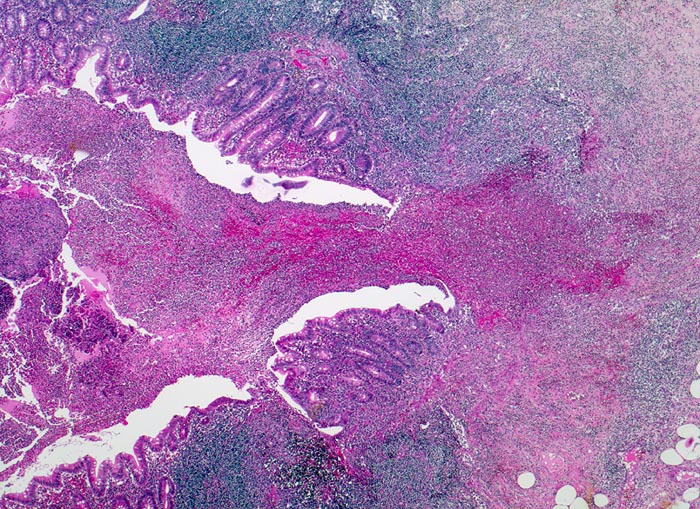

akute eitrige ulzerophlegmonöse Appendizitis: Ulkus

Appendix vermiformis

Rechts im Bild ein Ulkus. Daneben erhaltene Kolonmukosa. Die Appendixwand ist diffus entzündlich infiltriert.

Seit 6 Stunden Schmerzen im Unterbauch rechts mit zunehmender lokaler Druckempfindlichkeit. Übelkeit.

Histologie

25